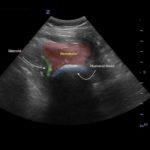

Bedside ultrasound with the transducer placed on the posterior right shoulder revealed an anterior dislocation of the right humerus. This is evident by displacement of the humeral head further away from the posteriorly placed ultrasound transducer, and appears deep to the glenoid cavity. In a posterior shoulder dislocation, the humeral head would appear closer to the transducer (and the near field of the ultrasound image) than the glenoid. Note that a hypoechoic, heterogeneous fluid collection is within the joint space, compatible with a hematoma. A right shoulder X-ray confirmed the anterior dislocation with no evidence of fracture. Under direct ultrasound guidance the glenohumeral joint space was injected with 10 mL of 2% lidocaine as an intraarticular anesthetic block. The right shoulder was reduced using continual traction. Post-reduction ultrasound demonstrated a successful shoulder reduction, depicted by the humeral head being relocated to its anatomical location, adjacent to the glenoid cavity, as noted on the ultrasound image. A hematoma remains present within the joint space. Successful shoulder reduction was further confirmed by X-ray. The patient’s arm was placed in a sling and she was discharged home with orthopedics follow-up.

Ultrasound guided intra-articular joint injections are best performed with the linear or curvilinear probe. With the probe on the patient’s lateral or posterior shoulder, locate the humeral head and the glenoid cavity. Determine the depth of the space and select a needle long enough to reach the cavity. Utilizing sterile technique, first place superficial local anesthetic. Then, advance the needle into the glenohumeral joint space and inject 10 to 20 mL of a local anesthetic, typically 1 or 2% plain lidocaine. An increase in anechoic space may be visible as the anesthetic is injected. The effect of the anesthetic should be active in about ten minutes.2,12